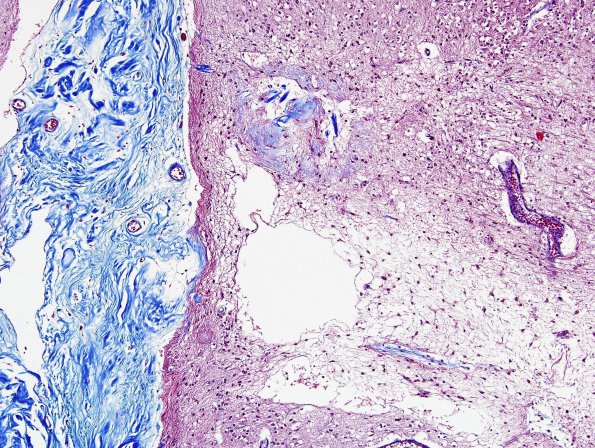

Neurosarcoid - no PNS

2E2 Neurosarcoid (Case 2) N5 Trichrome 2

Closeup of cortical infarct and leptomeninges (Trichrome stain)